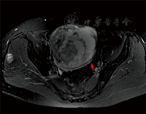

患者,女,64岁,孕5产2。2007年前自然绝经,绝经后无异常阴道出血及流液,2016年前因"子宫肌瘤"及"卵巢囊肿"在外院开腹行全子宫切除术、左侧附件切除术及右侧输卵管切除术。因"发现腹部包块3周,伴下腹坠胀感"于2017年5月27日收入本院。入院体查:T 36.4 ℃,P 78次/min,R 18次/min,BP 150/80 mmHg(1 mmHg=0.133 kPa),精神欠佳,心肺未见明显异常,下腹可见一纵行长约13 cm手术瘢痕。行妇科检查示外阴已婚型,阴道残端愈合可,右侧附件区可扪及一大小约13 cm×14 cm包块,质硬,边界清,活动度差,无明显压痛,双侧腹股沟无淋巴结肿大。妇科超声提示盆腔内可见两个囊实性回声,右侧大小约13.1 cm×11.9 cm×10.0 cm,边界清,以低回声为主,内可见多发不规则无回声区,CDFI:其内可见少许血流信号,RI:0.46,左侧大小约5.5 cm×5.0 cm×4.6 cm,边界清,可见低回声及多发不规则无回声区,CDFI:其内可见丰富血流信号,RI:0.22。盆腔MRI示盆腔内巨大囊实混合性占位,考虑双侧附件来源于囊腺癌可能性大,伴右侧髂内淋巴结肿大,右侧臀肌间隙结节灶,考虑血管瘤可能性大,子宫切除术后表现,见图1。胸片未见明显异常。肿瘤标志物:CA125:67 U/ml(正常值:CA125<35 U/ml),CEA、CA199、HE4、AFP无明显异常。